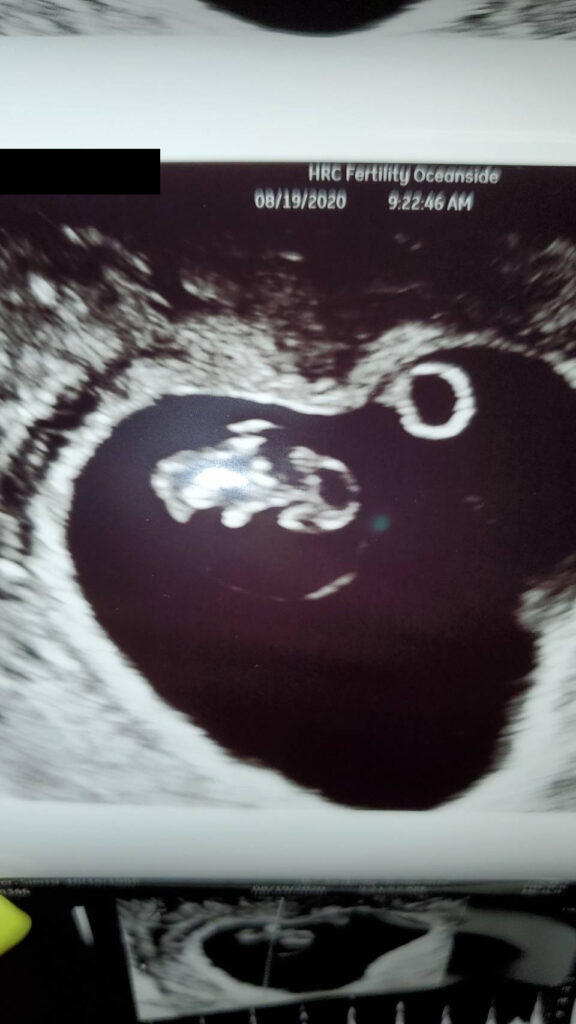

Baby超音波紀錄 : 5週又5天 Posted on August 25, 2020 by yourtesttubebaby 五個禮拜又五天大的小baby就是長的這樣的! ☀ 網站上每位小寶貝都是我們的成功案例,照片皆經父母親許可使用 ( 若未經允許請勿轉載 ) ☀ Posted in Uncategorized